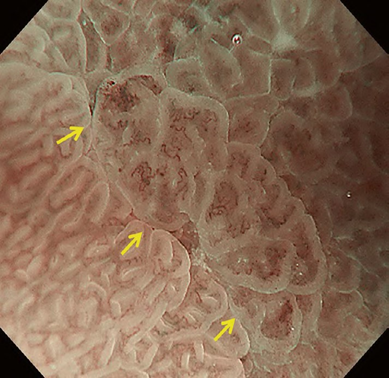

According to the morphology of the anatomical components, the MV and MS patterns were classified as regular, irregular, or absent (. Fig. 2). In principle, the MV and MS patterns must be determined separately.

DL is defined as the border between the lesion and non-lesion areas, discernible through an abrupt change in MV and/or MS patterns (. Fig. 2).

The working group members carried out a systematic review of the English literature to determine widely accepted diagnostic systems. Consequently, the best-accepted diagnostic system was proven to be the VS classification system. Based on this system, MESDA-G was constructed using an evidence-based approach (. Figs. 3, 4, 5, and 6) [2]. First, lesions suspicious for EGC should be detected by careful inspection using conventional white-light endoscopy. Subsequently, magnified observations should be performed. Owing to the high sensitivity of the demarcation line [8], if it is absent, the suspicious lesion is diagnosed as noncancerous (. Fig. 4a, b). However, if the demarcation line is present, further assessment is required to determine the presence of an irregular MV or MS pattern. If an irregular MV and/or MS pattern is detected, the suspicious lesion is diagnosed as cancerous (. Fig. 6a, b) [1, 5, 6, 8]. If both the irregular MV and MS patterns are absent, the tumor is diagnosed as noncancerous (. Fig. 5a, b) [1, 5, 6, 8].